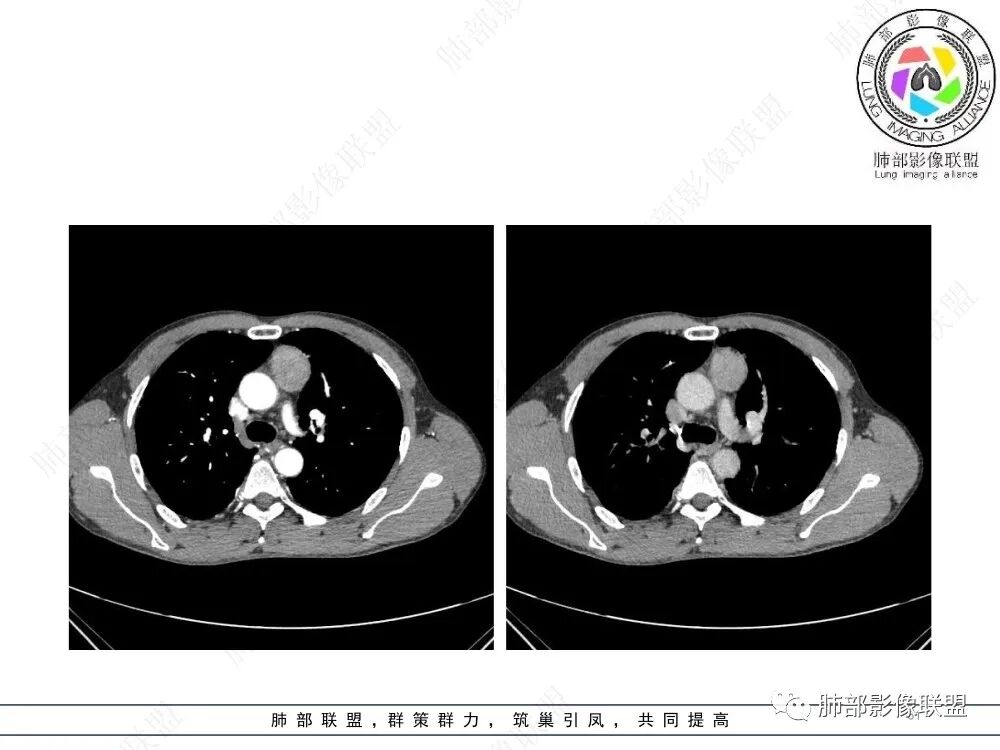

流心明智:男,47,咳嗽、咳痰1年余。胸部CT:前纵膈偏左类圆形肿块,瘤肺界面清晰光整,纵隔侧部分层面絮状影?平扫密度较均匀,增强后轻度强化,内可见宽带及线样低密度分隔。邻近左上肺受压凹陷。考虑胸腺肿瘤,AB型?胸腺Ca?鉴别淋巴瘤、N源性肿瘤、CD等。

在路上:考虑胸腺瘤,密度均匀,无钙化,轻度强化,边缘请放射线:前纵膈偏左侧肿块,边缘光滑清晰,周围脂肪间隙清晰,渐进性强化,密度不均,考虑胸腺瘤,鉴别淋巴瘤。

南边:支持前纵隔、胸腺瘤首选,晨读其实定位上还是有点难度,定性常规还是考虑胸腺瘤,其他的几率比较低一些,需要鉴别的是胸膜SFT,神经源性,可惜的是没重建,一直在犹豫胸膜来源的可能性。

2、影像特点:前纵隔偏左侧软组织影,密度相对均匀,未见明显包膜钙化及实质内钙化,局部边缘浅分叶,周围脂肪间隙密度增高、浑浊,未见侵犯大血管、未见纵隔内淋巴结转移、未见侵犯心包内结构、未见胸膜转移结节、未见肿块沿着纵隔胸膜蔓延,未见胸腔积液。增强后动脉期不均匀强化,未见明显纤维分隔。

3、 病 例 小 结:40岁以上,前纵隔偏侧性生长的肿块,常规考虑胸腺瘤。难点就在于胸腺瘤的分型。但是对于前纵隔占位影像诊断的关键在于区分胸腺囊肿、胸腺瘤、胸腺癌及其他恶性肿瘤。至于胸腺瘤,主要在于判断有无侵袭性。